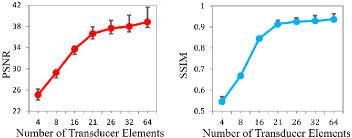

To analyze the impact of element down sampling rate on the reconstruction performance, we conducted PAT image reconstructions with varying numbers of transducer elements. We have tested transducer settings of Nd = 4, 8, 16, 21, 26, 32, and 64 elements, and the obtained quantitative PSNR and SSIM results with respect to the transducer with Nd=128 are presented in Fig.9. As can be seen, as the number of transducer elements used in the measurement increases, both PSNR and SSIM increase accordingly. Specifically, optimal image quality is achieved when Nd is larger than 21. When a smaller number of elements is used, both PSNR and SSIM decrease rapidly.